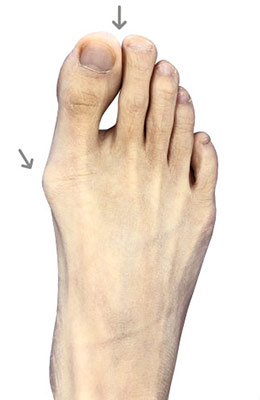

Minimally Invasive Bunion Surgery featuring the CrossRoads miniBunion™ System

Eva is a 24-year-old female who had just began working at a job that required high fashion shoes. She was in constant pain but could not take time off work. Our miniBunion™ Minimally Invasive Bunionectomy allowed her to continue to work and be on her foot with full recovery and return to regular shoes by 6 weeks. She had an amazing range of motion, no more bunion pain, and absolutely no visible incision. After picture taken six weeks post-surgery.